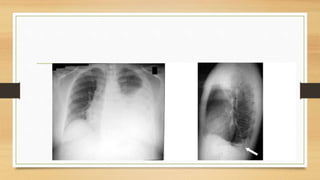

• La radiografía posteroanterior y lateral de tórax por lo general confirman la

presencia de un derrame pleural; cuando hay dudas, la ecografía o la

tomografía computarizada pueden detectar de forma definitiva el derrame

pleural.

• Pequeñas cantidades de líquido pleural pueden no ser vistas en una

proyección estándar frontal, pero pueden ser visualizadas mejor en una

proyección de decúbito lateral con rayo horizontal.